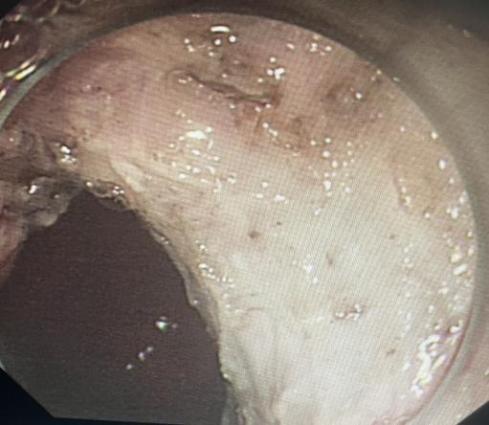

12月9日,张绍仁和周春华在消化内镜中心对患者进行放大内镜检查。经过评估,他们认为自己有内镜下治疗的指征,并决定进行消化内镜ESD手术治疗。手术持续了5个小时,张绍仁彻底剥离了病人的疾病,保留了整个胃,避免了手术的巨大创伤。术后患者恢复良好,一周后顺利出院。